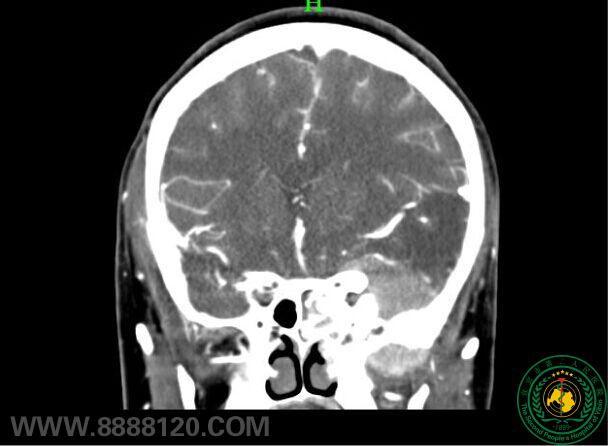

图示两例患者术前肿瘤位置

患者1

术后复查头颅CT示:术后骨瓣及颧弓复位良好

新手术入路完成颅内外沟通肿瘤切除术两例